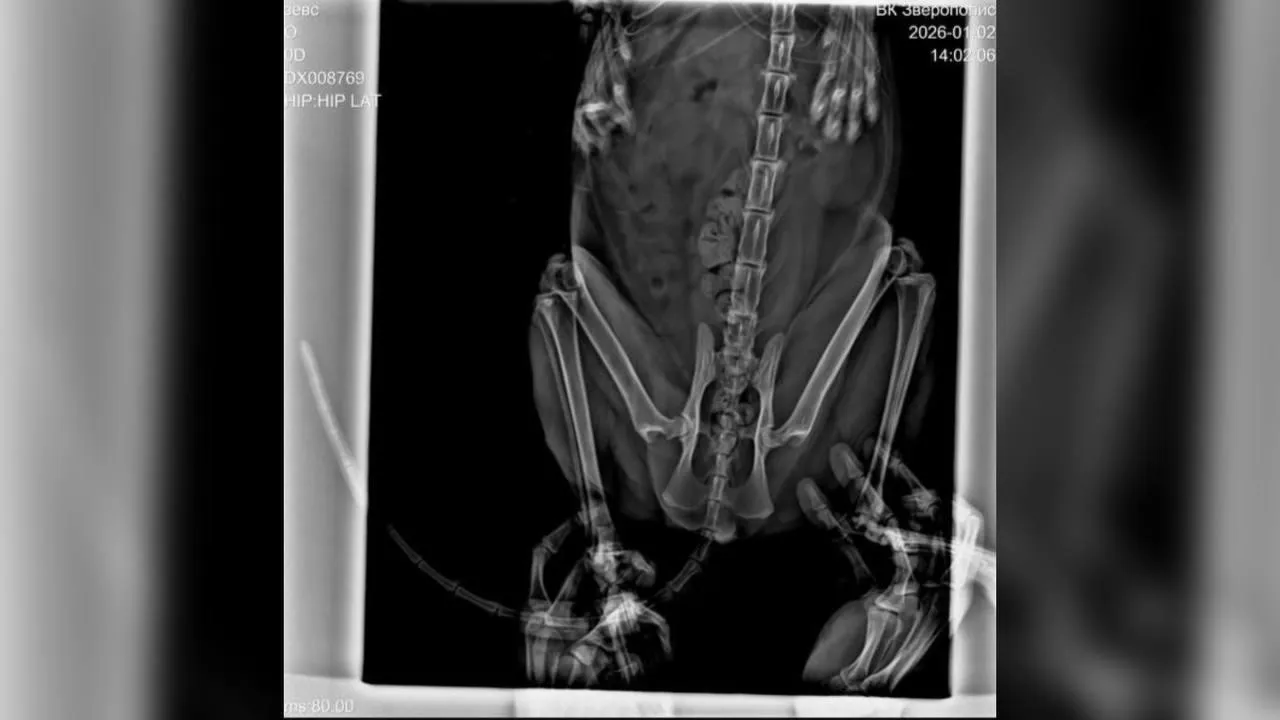

Из-за врожденной слабости организма у кота периодически возникали проблемы с суставами. Владельцы решили провести профилактическое хирургическое вмешательство, чтобы в будущем облегчить ему жизнь. Клинику в Набережных Челнах выбрали по рекомендациям — из-за наличия современного оборудования и КТ.

По ее словам, перед операцией владельцев не предупредили о рисках летального исхода, а с анестезиологом они так и не встретились. Изначально обсуждалась операция на двух суставах, однако в день вмешательства врач в одностороннем порядке принял решение оперировать только один — без подробных объяснений. Оплату за операцию попросили внести заранее.